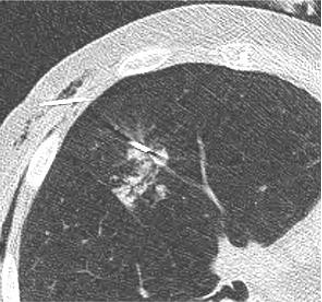

肺活检:小病变穿刺

双针技术 Fix lung area near small lesion with thin puncture needle first, then biopsy target lesion (tandem-technique) 先用细穿刺针固定小病变附近的肺区,再用活检针穿刺病变(双针技术)

双针技术

Fix lung area near small lesion with thin puncture needle first, then biopsy target lesion (tandem-technique)

先用细穿刺针固定小病变附近的肺区,再用活检针穿刺病变(双针技术)